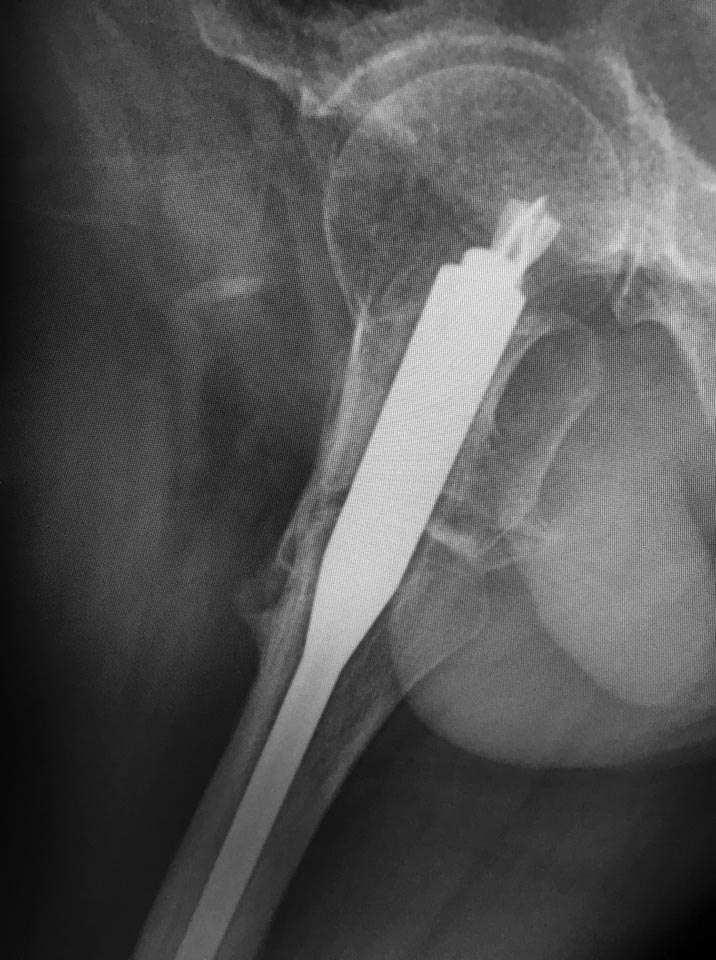

доброго времени суток! как бы вы поступили в данном случае? Пациент 52

года, синтез 7 мес назад, ходьба с костылями.

Боль при ходьбе. Два дистальных блокируемых винта в статике (

срезалось на фото)